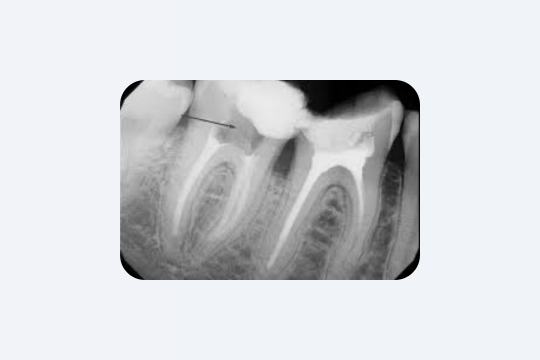

1. Глубокий кариес под пломбой

Под старой пломбой может годами «скрываться» глубокий кариес, который не вызывает боли, пока не достигнет пульпы зуба. Фактически почти две трети всех реставраций — это замена старых пломб из-за вторичного (рецидивирующего) кариеса.

Проблема в том, что поражение под пломбой не видно в зеркало и оно не беспокоит пациента, пока не станет серьёзным.

Только рентгеновские снимки (bitewing или периапикальные) могут выявить разрушение под реставрацией. Поэтому врачи говорят: рецидивный кариес часто обнаруживается случайно, при рентген-диагностике или во время удаления пломбы. Именно поэтому на плановом осмотре стоматолог обязательно проверяет старые реставрации и делает рентген, даже если пациента ничего не беспокоит.